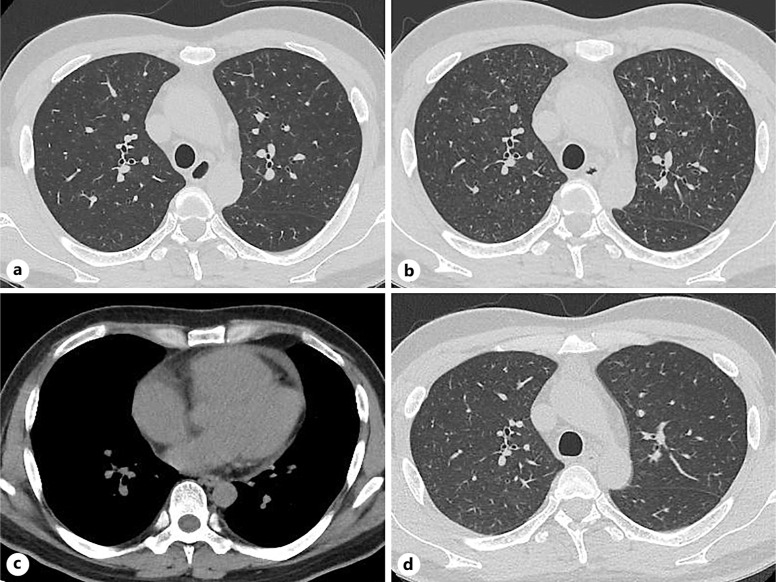

Case presentation: A 40-year-old man with advanced gastric adenocarcinoma on paclitaxel plus ramucirumab developed a dry cough and, after 2 months of a stable period, dyspnea on exertion. Chest computed tomography (CT) showed bilateral diffuse patchy ground-glass opacities (GGOs). Transbronchial biopsy revealed alveolar hemorrhage and small pulmonary arteries occluded with fibrocellular intimal proliferation, but no tumor cells. Suspecting chemotherapy-induced lung injury, we discontinued the chemotherapy and monitored him carefully without treatment. However, his dyspnea worsened, and follow-up chest CT showed worsening GGOs and right atrial and pulmonary arterial dilatation. Ultrasound cardiography indicated reduced right ventricular function. Lung perfusion scintigraphy confirmed numerous bilateral defects. Right heart catheterization revealed pulmonary hypertension, but no tumor cells on pulmonary wedge aspiration cytology. We clinically diagnosed the patient with PTTM. Three weeks after his initial visit for dyspnea, he was started on nivolumab. One week after treatment, he required home oxygen therapy at 1 L/min on exertion. After two doses of nivolumab, he no longer had dyspnea and discontinued oxygen therapy. Follow-up ultrasound cardiography showed normal pulmonary arterial pressure, and almost all GGOs on chest CT were resolved.